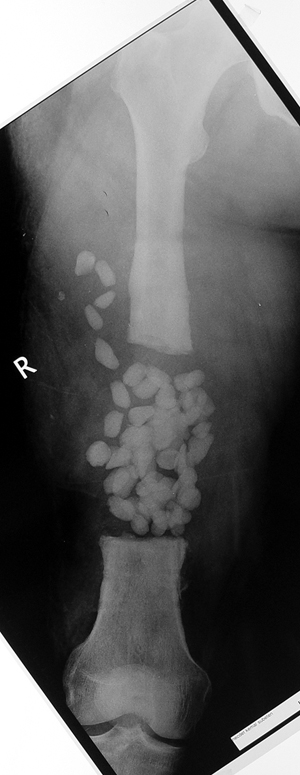

Chronic osteomyelitis leads to necrosis of bone and soft tissues. Dead bone is a nidus which hosts pathogenous microorganisms. Defence mechanisms of the host is usually not in optimum condition to deal with microorganisms. Antibiotics can’t reach the infection site because blood flow is disrupted. For these reasons, dead bone has to be completely removed by radical debridement.

Appropriate radical debridement necessitates excision of all necrotic bone and soft tissues, and frequently causes instability at the involved extremity. The remaining bone and soft tissue defect has to be fixed and reconstructed. The distraction osteogenesis method of Ilizarov is used successfully for achievement of union, correction of the deformity, elimination of limb length inequality and reconstruction of segmental bone defects.